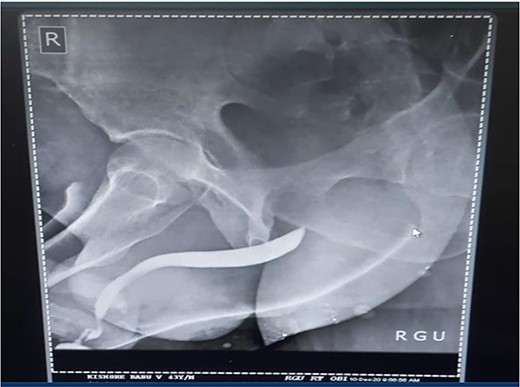

A 37-year-old male presented with a history of a ‘snap’ sound and immediate detumescence of penis during intercourse, when he fell and hit the pubic bone of his partner. There was generalized swelling and pain in the penis. There was acute retention of urine, an attempt to pass a catheter failed and the patient underwent supra-pubic catheterization. On examination, there was classical ‘eggplant deformity’ of the penis with blood at the tip of the meatus. MRI showed a tunical tear on both sides at the penoscrotal junction with indistinct urethra and extensive hematoma in the proximal penile shaft (Fig. 1). With the diagnosis of a fractured penis and possible urethral injury, after proper counselling, the patient was taken up for surgery. On the table, a retrograde urethrogram (RGU) was done showing evidence of partial urethral disruption. On exploration with penoscrotal vertical incision, there was total transection of proximal penile urethra, and a 1.5 cm tunical injury of corpus cavernosum on both sides ventrally (Fig. 2). There was extensive hematoma. Corpora sutured with 4.0 prolene after reconstructing the midline septum. Urethral ends mobilized and anastomosed with 3.0 vicryl in a single layer with minimal spatulation (Fig. 3). The patient was discharged on the 5th post-operative day; Foley catheter was removed on day 21. Follow-up RGU done after 3 months showed no evidence of stricture (Fig. 4).

(1) On table RGU showing evidence of partial urethral disruption and (2) total transection of proximal urethra on exploration with penoscrotal vertical incision.

Penile fracture is an uncommon urological emergency that occurs when the tunica albuginea in an erect penis rupture due to excessive external bending stress during sexual activity and the injury is most caused at the time of coitus [1, 2]. Other less common causes are masturbation and the practice of Taqaandaan [3, 4]. In most cases, a penile fracture results in a cracking sound, fast detumescence, abrupt enlargement and ecchymosis of the penis, which gives it the appearance known as ‘eggplant deformity’ [5]. The rupture occurs more often in the proximal shaft and is located ventrally in coital injuries. In our case, there was a bilateral corporal tear. Literature states that bilateral corporal ruptures are often accompanied by urethral injury [6]. Urethral rupture, although infrequent, has an incidence that varies between 1 and 38%. This rupture may be partial or complete [7, 8]. Blood in the meatus, hematuria and voiding symptoms are highly indicative of urethral rupture, but the absence of these findings does not exclude urethral lesions [9]. Our patient presented with swelling, pain and acute retention of urine, which was followed by a failed attempt at urethral catheterization and on examination of the penis, we found blood at the tip of the meatus. All these findings yielded a high suspicion of urethral injury and we decided to perform an RGU. In suspected cases of urethral injury, RGU may demonstrate contrast leakage at the lesion site and reveal the exact point of urethral injury. However, RGU can show false negative results in up to 28.5% of cases [10]. In this case report, RGU could only show evidence of a partial rupture but, intraoperatively, there was found to be a complete transection of the proximal penile urethra. Compared to the traditional non-operative options, surgical restoration of the tear has proven to provide patients with the greatest results in terms of both sexual function, cosmetic appearance and fewer complications [9, 11, 12]. Penile degloving using a circumferential or subcoronal incision is the most used technique followed by penoscrotal and longitudinal incisions directly over the hematoma. The sub-coronal degloving incision is useful in cases with significant penile swelling or extensive hematomas, as well as in cases where the location of tunical rupture cannot be determined clinically or radiographically, or when the rupture is located dorsally [13]. Major disadvantages of the sub coronal degloving incision are the extensive dissection of Buck’s fascia and its risk of distal penile/preputial skin necrosis. In this case, we performed a penoscrotal incision. We chose this technique because it gives easy exposure to the base of the corpora cavernosa where fractures tend to occur more often and in addition would give us direct access to the urethral transection. With the penoscrotal incision, we have the flexibility of extending the incision and can also avoid futile dissection in the buck’s fascia [13]. We reconstructed the midline septum and closed the corpora using 4.0 prolene. Urethral ends were mobilized and anastomosed with 3.0 vicryl in a single layer with minimal spatulation. The patient was discharged on the 5th postoperative day, and the Foley catheter was removed on day 21. A follow-up RGU performed after 3 months showed no evidence of stricture.